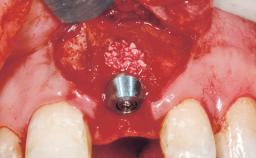

Immediate Flapless Placement of an Implant in a Maxillary Right Lateral Incisor Site

Placement Protocol Immediate implant placement

Tooth Site Maxillary incisor or canine

Socket Morphology Single-root socket

Socket Integrity Sufficient, with intact bone walls

Bone Volume Sufficient, with intact walls

Loading Protocol Immediate